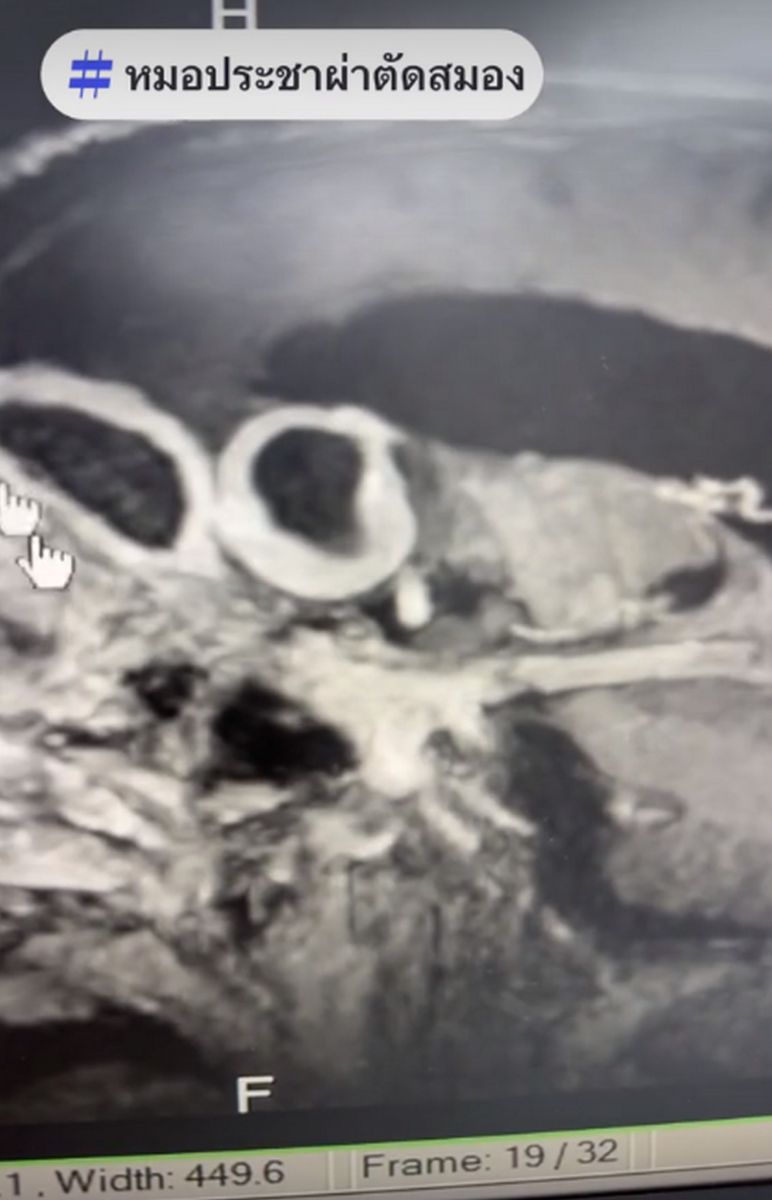

5 กรกฎาคม 2567 นพ.ประชา กัญญาประสิทธิ์ หรือ หมอประชาผ่าตัดสมอง ศัลยแพทย์ผู้เชี่ยวชาญระบบประสาท โรงพยาบาลเชียงใหม่ราม โพสต์เฟซบุ๊กฝากเป็นอุทาหรณ์ โดยเฉพาะ โรคไซนัส รายละเอียดระบุว่า "ไซนัสไม่ดีทำให้เป็นฝีในสมอง" สำหรับคนที่มีอาการไซนัสอักเสบ เสี่ยงเกิดฝีในสมอง อันตรายถึงตาย พร้อมยกเคสผู้ป่วยชายวัย 69 ปี มาโรงพยาบาลด้วยอาการไข้ ปวดศรีษะ ซึมลง ผลเอกซเรย์สมองพบว่า ส่วนหน้าซ้าย บริเวณหน้าผากมีฝีอยู่ 2 ก้อน คนไข้ให้ประวัติว่า ป่วยเป็นไซนัสอักเสบมา 1 เดือน มีไข้สูงขึ้นเรื่อย ๆ ปวดศรีษะ สุดท้ายกลายเป็นฝีในสมอง

ความอันตรายของฝีก้อนนี้ คือ ถ้าแตกเข้าไปในช่องน้ำเลี้ยงสมอง ร้ายแรงถึงขั้นเสียชีวิตได้ หมอจึงได้ผ่าตัดเอาก้อนฝีออก ภายในก้อนฝีจะเห็นคล้ายกับเป็นนมข้นหวาน ซึ่งคือหนองล้วน ๆ ผลซีทีสแกนหลังผ่าตัด ซึ่งหมอได้ดูดเอาหนองออก เลาะโพรงผนังของหนองออกไป โดยยังเหลือผนังที่ติดกับช่องน้ำเลี้ยงสมองไว้ เพราะเป็นส่วนที่อันตรายมาก ถ้าแตกเข้าไปในช่องน้ำเลี้ยงสมอง อาจร้ายแรงถึงตายได้ เคสนี้ต้องรักษาด้วยการให้ยาฆ่าเชื้อต่ออีกหลายสัปดาห์ จากนั้น MRI หรือซีทีสแกน ซ้ำ ถ้าหายแล้วจึงจะหยุดยาได้